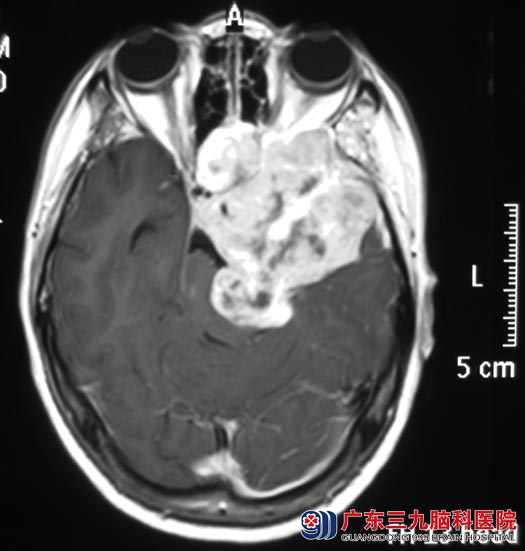

吴女士2年前出现左侧颜面部麻木感、如蚂蚁爬行感;一周前突然出现视物重影,伴头痛头晕,当地医院头颅CT显示:左侧中后颅窝巨大占位。广东三九脑科医院头颅MR检查提示:左侧中、后颅窝颅内外区示一巨大占位病灶,大小约77.5mm×70.8mm×45.2mm,累及左侧颞下窝及翼腭窝、左侧颞部,向前向下突入上颌窦内,向内突入蝶鞍、蝶窦、筛窦内,左侧眶尖受累,向后突破岩尖伸入后颅窝左侧桥小脑角区,邻近脑干明显受压变形、移位,四脑室变形、稍变窄。CT提示相应骨质呈膨胀性的吸收破坏。